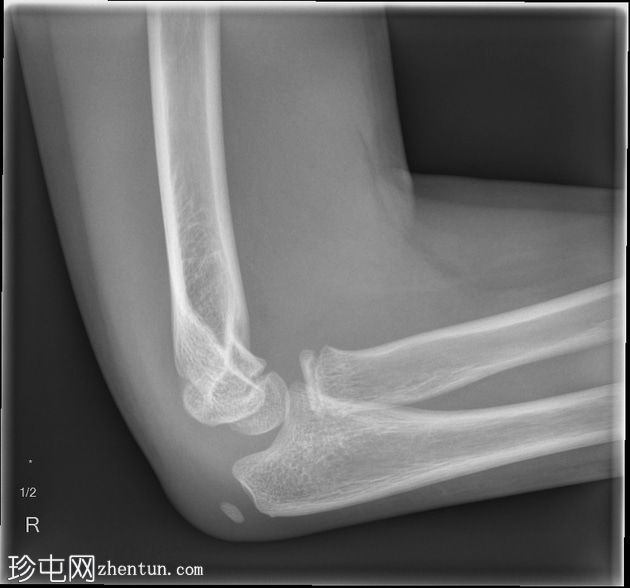

肘关节X线片

X线片

1.jpg

侧位片

内上髁附近可见骨碎片,内上髁轻度移位。上方软组织中度肿胀,前脂肪垫隆起,提示关节积液。影像表现符合内上髁撕脱性骨折。关节对位正常。

桡骨头骨骺可见正常变异裂隙。